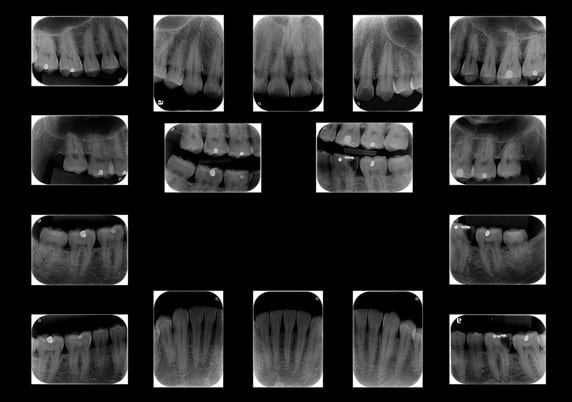

Levantamento Periapical